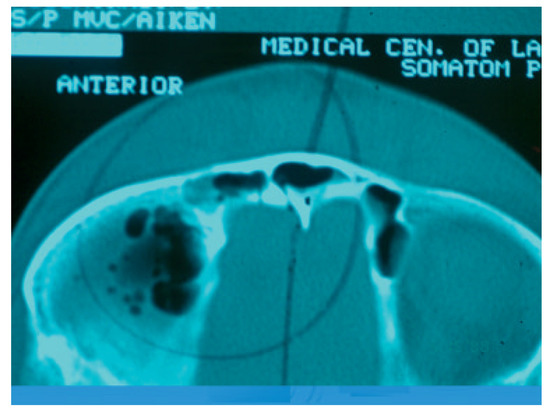

Frontal sinus fractures are usually caused by anterior blunt force trauma. The majority of these injuries are secondary to motor vehicle accidents (Figure 1) [1,2,3]. With the advent of mandatory seatbelt laws and airbags, we have seen a decrease in frontal sinus fractures by motor vehicle accidents but an increase in fractures by interpersonal violence (blunt and penetrating), sports injuries, falls, and falling objects [3,4,5]. The choice of treatment is usually dictated by the site and extent of the damage. Concomitant injuries also play a role in treatment selection as well as timing of repair. This is important because inadequate or delayed treatment can lead to immediate and/or long-term complications [6,7].

Figure 1.

Photograph of patient involved in a motor vehicle accident with open, linear, minimally displaced anterior table frontal sinus fracture. This is the usual presentation for an open frontal sinus fracture with the usual orbital, maxillofacial, neurologic, and ophthalmologic sequelae.